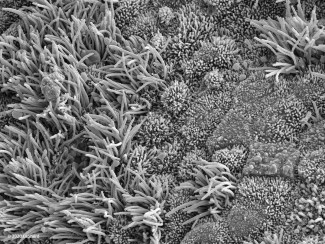

COVID Infected Nasal Epithelial Tissue